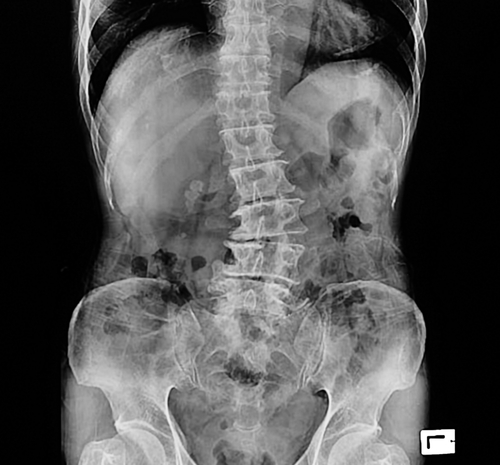

A 17-year-old girl from Poland, who suffered sideways curves in spine, also known as scoliosis, has been cured at a city hospital here through a surgery with spinal navigation -- a technique that helps surgeons guide their instruments for more precise screw placement.

Problem for Agnes started after she developed a hump on the right side of her back. Despite diagnosed of scoliosis and being clearly told that surgery was the only solution, Agnes did not want to undergo the treatment in her own country, as hospitals there did not have spinal navigation technique, which would make the surgery more risky.Accordingly, she and her parents learnt about Mumbai hospital and its expertise in treating scoliosis cases, and she admitted to the city-based hospital.Doctors said that the right shoulder blade was more prominently protruding along with waist asymmetry.

This had caused significant cosmetic deformity leading to loss of confidence and social stigma to the patient.As the condition was progressing with time, deformity correction and spinal fusion surgery was performed with the help of neuromonitoring and spinal navigation.The image-based technology used in spinal surgery utilises scans of the patient's anatomy and instruments that are tracked by the navigation system's camera. Navigation can help surgeons guide their instruments for more precise screw placement and assist in advanced procedures."Since the spine was totally deformed and crooked, the anatomy becomes extremely deranged in scoliosis. Insertion of pedicle screws, which forms the main powerful mechanism of scoliosis correction, becomes a challenge. Spinal navigation is a boon in such situations," said Arvind Kulkarni, Head of Mumbai Spine Scoliosis & Disc Replacement Centre, elaborating the surgery.